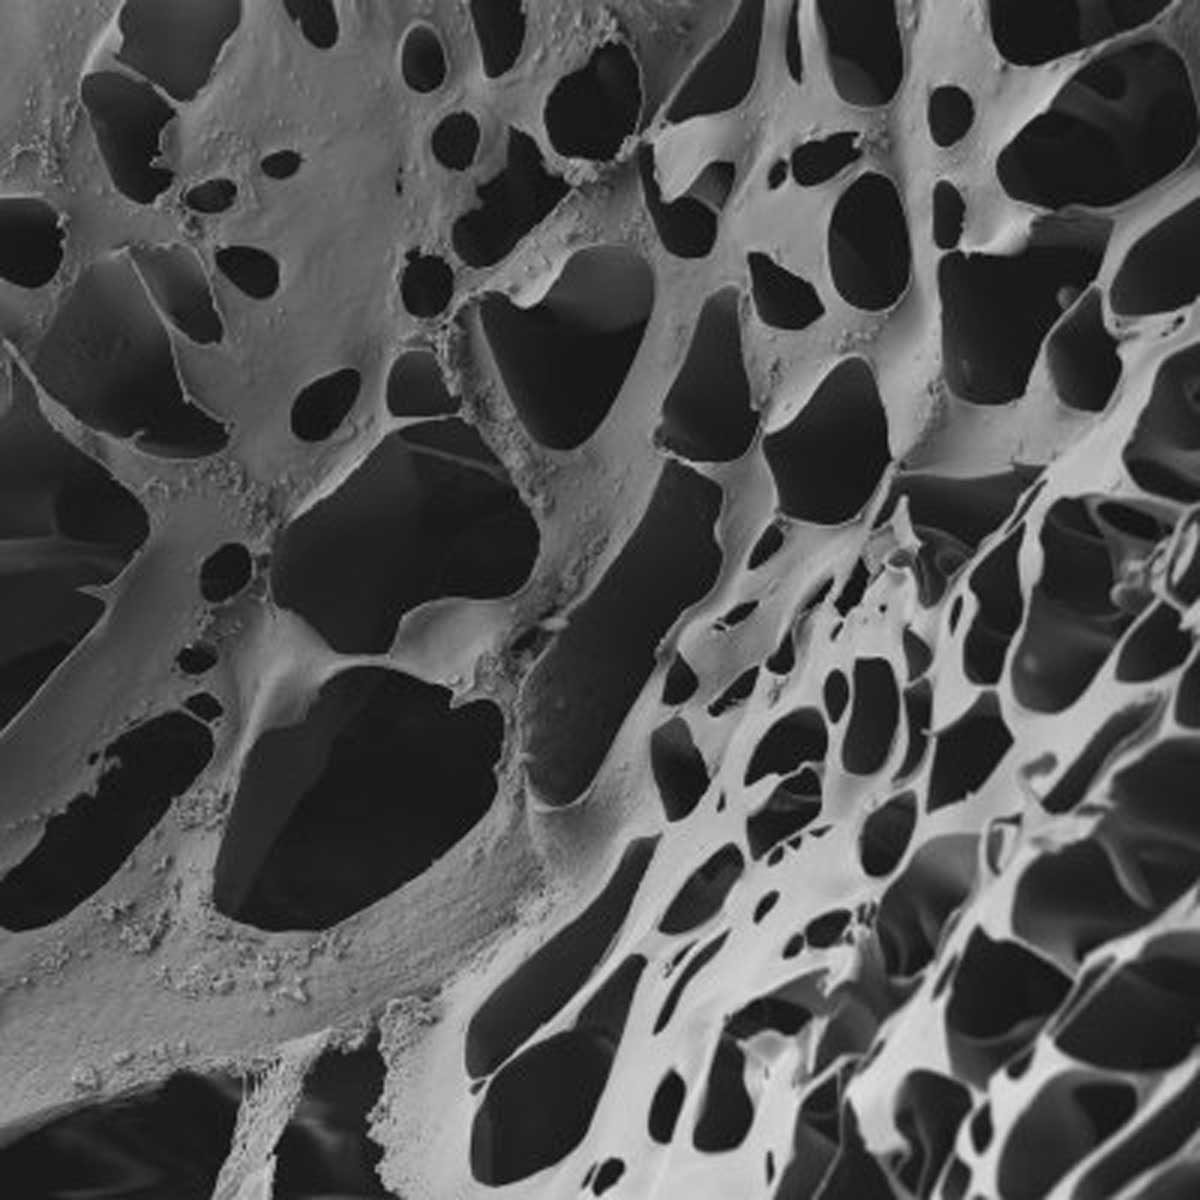

Supra SRDM CW ist eine synthetische Matrix, zu 100 Prozent bioabbaubar. Sie besitzt eine bimodale Schaum-Membran-Struktur und ist eng verwandt mit dem etablierten PMI-Produkt Suprathel, einem temporären Hautersatz, der mit über 20.000 Anwendungen pro Jahr längst Standard in der Behandlung von Verbrennungen ist. Supra SDRM CW ist eine dickere und porösere Form von Suprathel. Das ist vor allem beim Einsatz bei nässenden Wunden wichtig. Wenn die Wunde trocken wird, nimmt die Porengröße ab.